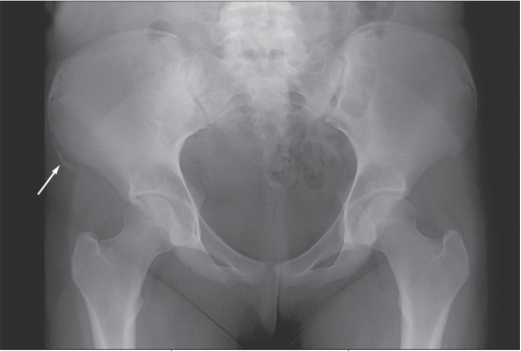

A 14-year-old girl came to the office with severe hip pain, which occurred after she attempted a cheerleading maneuver on a trampoline.